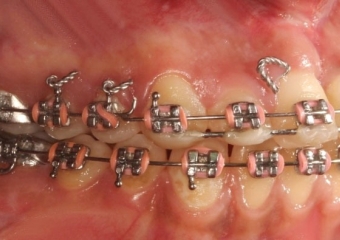

Mordida Inicial - Clínica Cliniface

Mordida Inicial